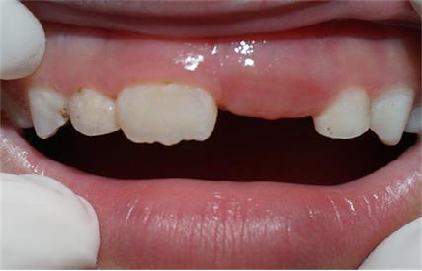

恒牙迟萌原因多种多样:

恒牙胚坏死、缺失或者错位。

多生牙、牙瘤或囊肿的阻碍。